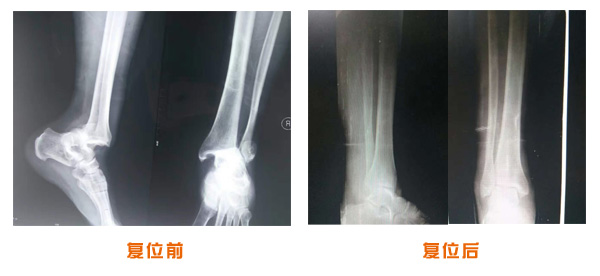

肥城市安駕莊梁氏骨科醫院是一所以梁氏手法正骨配合膏藥為特色的現代化??漆t院。

梁氏骨科術始創于清雍正年間,歷經八代,至今已有三百年歷史。據1929年泰安縣志載“梁瑞圖先生,字增生,號蓮峰,安駕莊人,精岐黃并發明接骨,凡跌打車凡跌打車軋皮不破而碎骨者......【詳細】 |